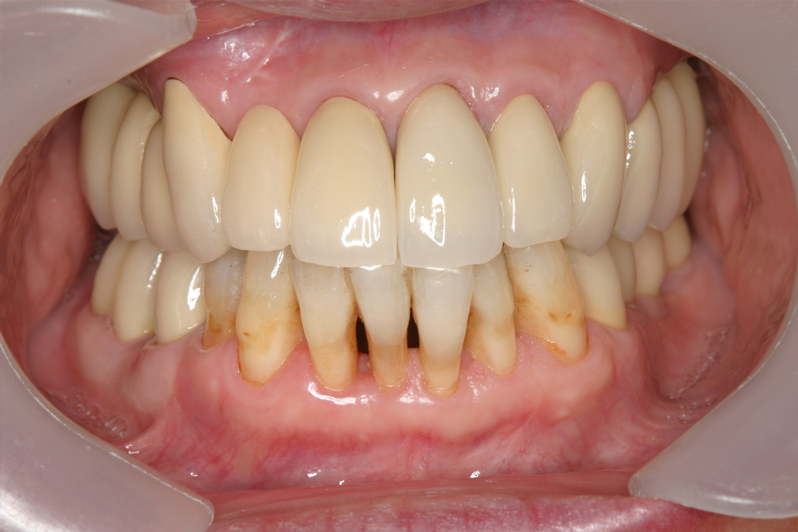

【受傷時 2018年5月17日】

【最終補綴物装着 2020年3月19日】

【受傷前口腔内写真】

【受傷後最終補綴物装着】

前歯の受傷前の歯肉の膨らみが、抜歯後にも変わらない状態を維持してインプラント治療されています。患者様、術者も結果がとても良いと満足しています。